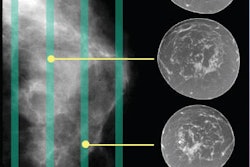

Swedish medical imaging and informatics vendor Sectra of Linköping has signed a partnership agreement with Kurt & Kurt, a Turkish medical distribution company.

Under the terms of the agreement, Ankara, Turkey-based Kurt & Kurt becomes a distributor of Sectra's PACS and digital mammography products in that country.